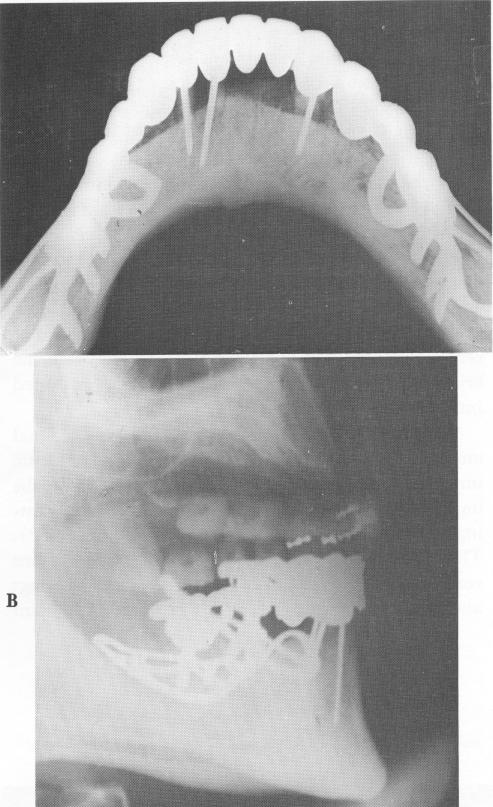

Fig. 12-69. A, A cross-sectional occlusal x-ray showing both subperiosteal implants in close position over the bone. Three endodontic root stabilizers were used to stabilize the three remaining anterior teeth. B, A lateral plate showing the subperiosteal implants and endodontic stabilizers in position.

Radiographs of the finished case are seen in Fig. 12-69.

1 X ray of mandibular subperiosteal implant & endodontic root stabilizer